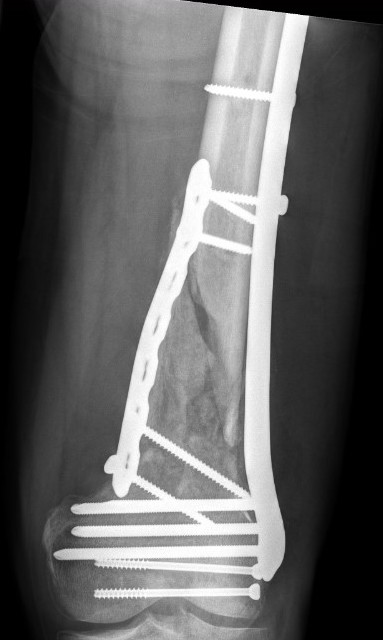

AO Type B1 & B2: Partial articular

![]()

Definition

Medial or lateral sagittal split

Technique

ORIF

- medial or lateral approach based on fracture location

- reduce articular split and fix with screws

- medial or lateral buttress plate

Lateral split fracture distal femur